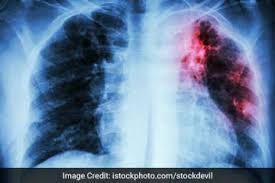

महासमुंद, 6 फरवरी 2026 : जिले में राष्ट्रीय क्षय उन्मूलन कार्यक्रम के अंतर्गत टीबी उन्मूलन के लक्ष्य को प्राप्त करने हेतु फरवरी 2026 से 100 दिवसीय विशेष अभियान प्रारंभ किया जा रहा है। कलेक्टर विनय कुमार लंगेह के निर्देशन में यह अभियान संचालित किया जाएगा। यह अभियान संयुक्त राष्ट्र संघ के सतत विकास लक्ष्यों (एसडीजी-2030) के अनुरूप जिले को टीबी मुक्त बनाने के उद्देश्य से संचालित किया जा रहा है।

आयुष्मान आरोग्य मंदिर स्तर पर संभावित टीबी मरीजों का निःशुल्क डिजिटल एक्स-रे एवं संदिग्ध मरीजों की नॉट जांच की जाएगी। निजी चिकित्सालयों को शत-प्रतिशत टीबी मरीजों की अधिसूचना प्रदान करने के निर्देश दिए गए हैं। साथ ही जन जागरूकता अभियान चलाकर जिले के नागरिकों, जनप्रतिनिधियों एवं अधिकारियों-कर्मचारियों से अपील की जाएगी कि वे निक्षय मित्र बनकर टीबी मरीजों को गोद लें, उन्हें फूड बास्केट उपलब्ध कराएं तथा उनके परिवारजनों की भी सहायता करें।